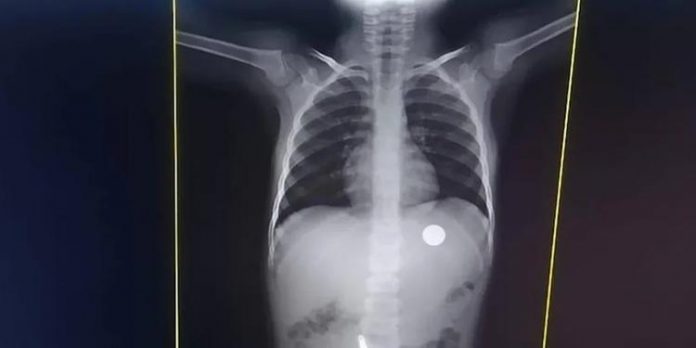

Menina de 4 anos engole moeda e tem dificuldade de respirar: ‘Mãe, vou morrer’